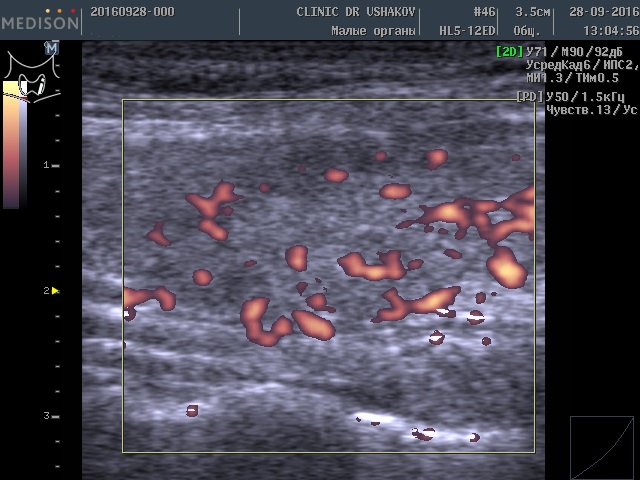

После 2-го курса лечения в «Клинике щитовидной железы» доктора А.В. Ушакова состояние гормонального обмена и самой щитовидной железы значительно улучшилось. Контрольный анализ крови показал (03.11.2016): ТТГ 5,76 мЕд/л (0,4-4,0), Т4св. 11,4 пмоль/л (9-22), Т3св. 4,0 пмоль/л (2,6-5,7), Т4общ. 89,2 нмоль/л (55-137). Как видите, восстановилось количество щитовидных гормонов, а стимуляция щитовидной железы существенно уменьшилась.

При контрольном УЗИ выявлена оптимизация объёма щитовидной железы. Уменьшился до 9 мл (оптимальный объём ЩЖ для этой пациентки 7-8 мл). При этом улучшилась состояние ткани (стал меньше признак лимфоцитарной инфильтрации ― распространённая гипоэхогенность (на снимке ― затемнение фона)). Заметно уменьшилась активность кровотока (рис. 7 и 8).

Рисунки 7 и 8. Пациентка К., 45 лет, левая и правая доли щитовидной железы в режиме ЭДК. После двух лечебных курсов, проведенных в Клинике доктора А.В. Ушакова. Кровоток (обозначен красным цветом) в умеренной и малой степени усилен.